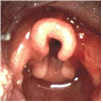

좌: normal

우: subglottic stenosis. 성대 너머로 성문하부가 좁아진 모습